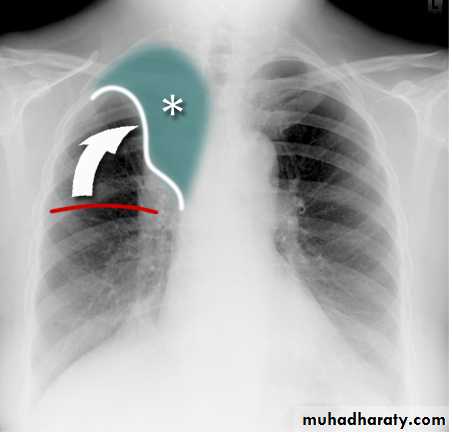

Thymoma.

A chest x-ray (A) reveals an unusual contour over the left hilum (arrows). That the hilum is not obscured (no silhouette sign) indicates that the mass must either be in front of or behind the hilum. A computed tomography scan (B) reveals a soft tissue mass (arrow) just to the left of the aorta. This is the most common location of a thymoma.